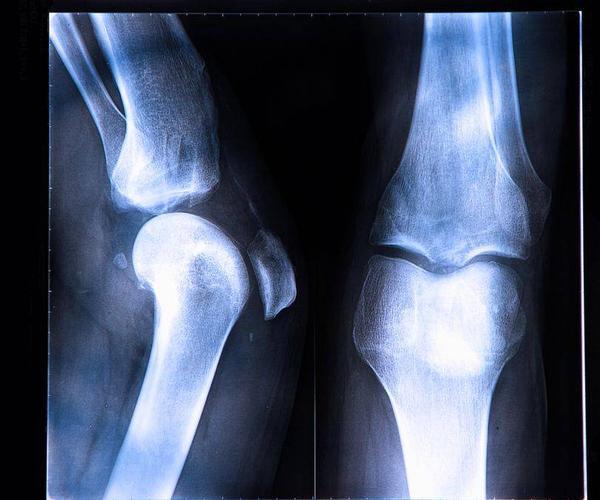

膝關節是人體最大和較爲複雜的關節,主要由三部分組成,即關節腔、骨關節、肌肉連接。

先說一下骨關節,他是一個滑車關節,主要涉及到髕骨、股骨的下部分、脛骨的上部分和半月板。再說一下關節腔,關節腔是有這些骨組織和一旁的肌肉及韌帶組成的腔隙,整體薄而鬆弛。

而關節腔裏面有一定的液體,也就是關節滑液,一般量爲4毫升或者更少。最後是韌帶,包括髕韌帶、腓側副韌帶、脛側副韌帶、斜韌帶、膝交叉韌帶等。